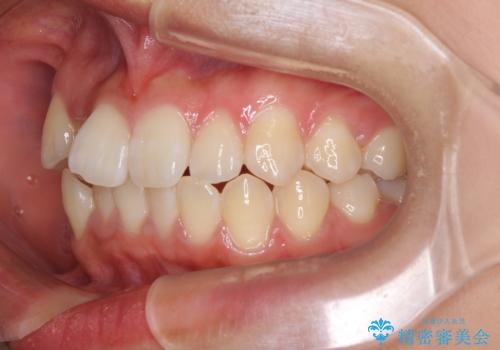

- 上下のデコボコと前歯のクロスバイトを改善したいとのことで来院された患者様です。

極力短期間で治療したいとのことで、ワイヤー装置による矯正治療を行うこととしました。

お住まいが遠方であったため、マウスピースによる矯正治療も提案しましたが、ご自身でのマウスピースの管理の面倒くささと、なるべく早く治療を終えたいとのことで、ワイヤー矯正を選択されました。